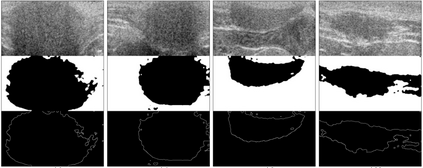

Biodegradable elastic scaffolds have attracted more and more attention in the field of soft tissue repair and tissue engineering. These scaffolds made of porous bioelastomers support tissue ingrowth along with their own degradation. It is necessary to develop a computer-aided analyzing method based on ultrasound images to identify the degradation performance of the scaffold, not only to obviate the need to do destructive testing, but also to monitor the scaffold's degradation and tissue ingrowth over time. It is difficult using a single traditional image processing algorithm to extract continuous and accurate contour of a porous bioelastomer. This paper proposes a joint algorithm for the bioelastomer's contour detection and a texture feature extraction method for monitoring the degradation behavior of the bioelastomer. Mean-shift clustering method is used to obtain the bioelastomer's and native tissue's clustering feature information. Then the OTSU image binarization method automatically selects the optimal threshold value to convert the grayscale ultrasound image into a binary image. The Canny edge detector is used to extract the complete bioelastomer's contour. The first-order and second-order statistical features of texture are extracted. The proposed joint algorithm not only achieves the ideal extraction of the bioelastomer's contours in ultrasound images, but also gives valuable feedback of the degradation behavior of the bioelastomer at the implant site based on the changes of texture characteristics and contour area. The preliminary results of this study suggest that the proposed computer-aided image processing techniques have values and potentials in the non-invasive analysis of tissue scaffolds in vivo based on ultrasound images and may help tissue engineers evaluate the tissue scaffold's degradation and cellular ingrowth progress and improve the scaffold designs.